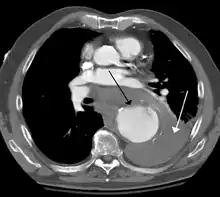

A thoracic aortic aneurysm is an aortic aneurysm that presents primarily in the thorax.

A thoracic aortic aneurysm is the "ballooning" of the upper aspect of the aorta, above the diaphragm. Untreated or unrecognized they can be fatal due to dissection or "popping" of the aneurysm leading to nearly instant death. Thoracic aneurysms are less common than an abdominal aortic aneurysm.[2] However, a syphilitic aneurysm is more likely to be a thoracic aortic aneurysm than an abdominal aortic aneurysm. This condition is commonly treated via a specialized multidisciplinary approach with both vascular surgeons and cardiac surgeons.

Diagnosis

Thoracic aortic aneurysm is defined as a cross-sectional diameter exceeding the following cutoff:

- 4.5 cm in the United States[7]

- 4.0 cm in South Korea[8]

A diameter of 3.5 cm is generally considered dilated.[7] However, average values vary with age and size of the reference population, as well as different segments of the aorta.